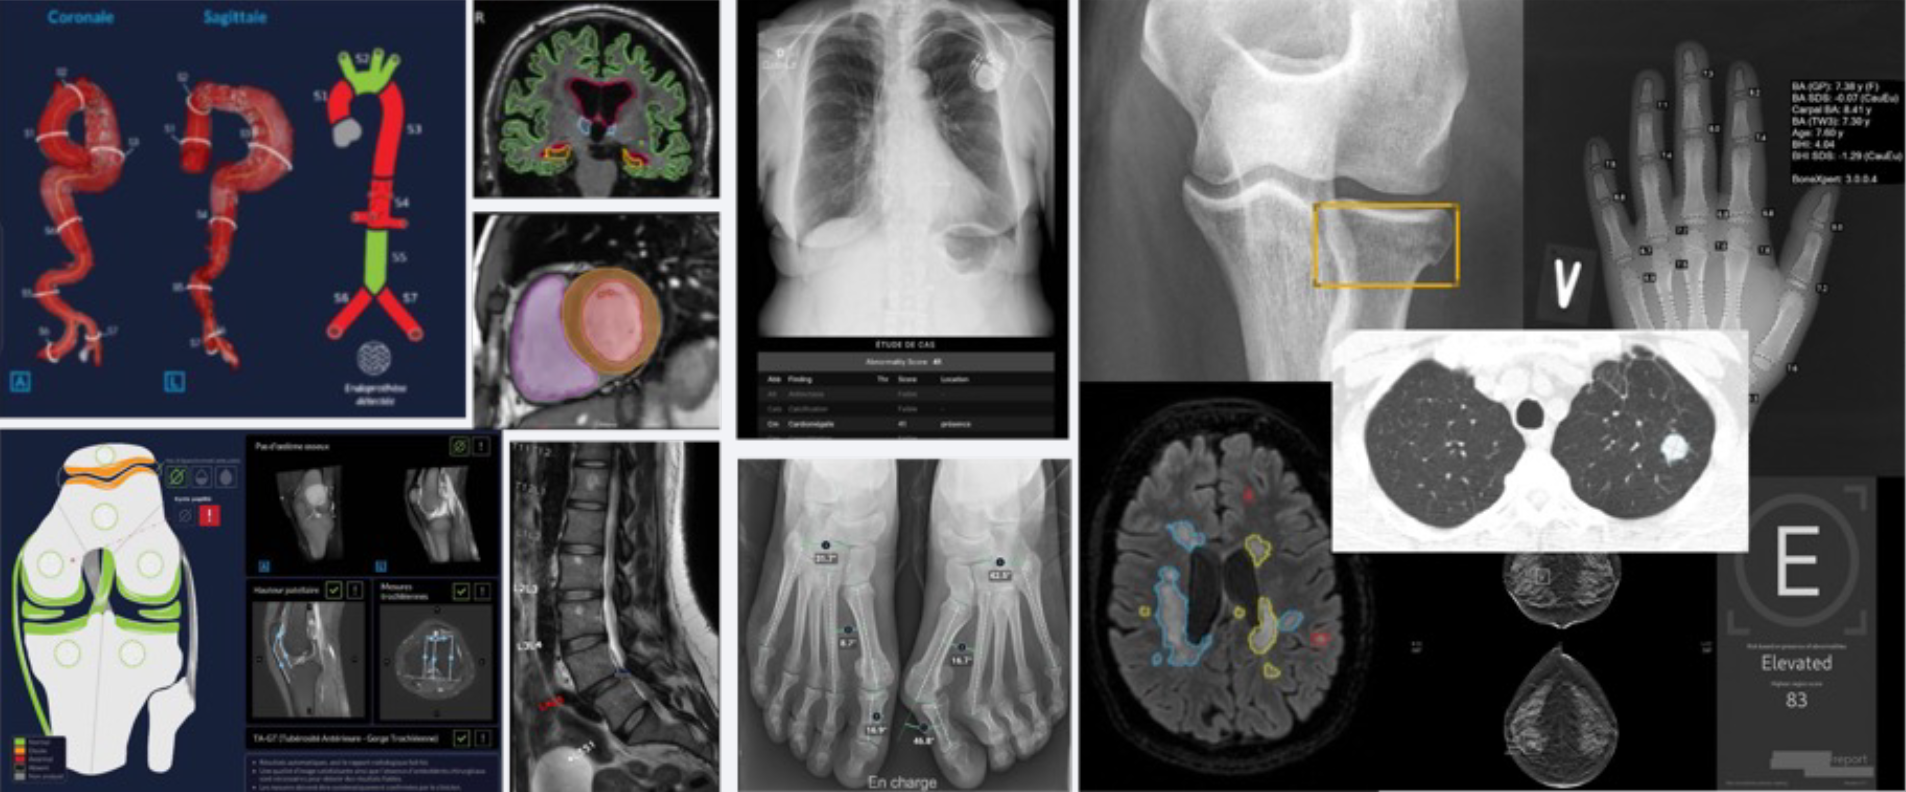

- Traumatologie/orthopédie : détection de fractures et mesures osseuses en quelques secondes, avec jusqu’à -60% de délai de compte rendu (Bonview)

- IRM du genou : pré-remplissage des comptes rendus structurés avec environ -30% de temps de lecture (Keros)

- Dépistage du cancer (sein, poumon) : aide à la détection précoce d’anomalies subtiles (Transpara, Veye Lung)

- Scanner CT : programme de réduction de dose avec jusqu’à -53% de risque radio-induit estimé sur plus de 11’000 examens